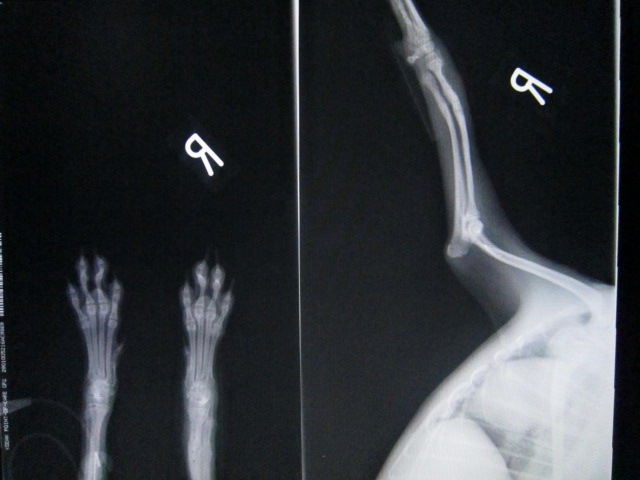

抜プレート後のレントゲンです。

骨折部位は少し太くなって治ります。